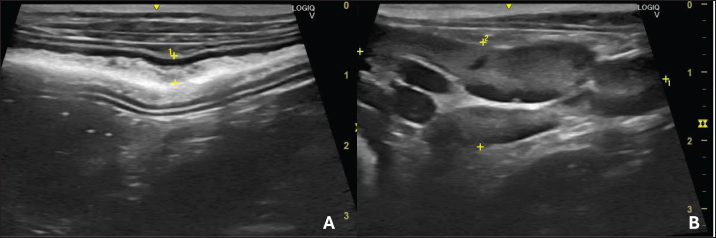

Strain elastography was performed using the same ultrasound machine with a linear transducer and a frequency of 10 MHz. The transducer was positioned on the animal’s abdomen, and then, five cycles of compression and decompression were performed. The color histogram was generated and superimposed on the duplicate B-mode image. This map generated images with a colorimetric scale ranging from blue to red for tissues with maximum stiffness, intermediate elasticity, and maximum elasticity.

For the static qualitative assessment, the proximal segments of the duodenum and jejunum were analyzed in a longitudinal ultrasound section, and a heterogeneous distribution was found between the dorsal and ventral regions of the intestine, with patterns ranging from predominantly blue with some greenish parts and reddish foci (Fig. 2). To obtain the semiquantitative parameters, the region of interest (ROI) was drawn using the device’s software cursor. Initially, a reference, ROI 1 was obtained in the mesentery adjacent to the intestines, and ROI 2 was drawn in the dorsal region of the duodenum and jejunum. The drawings were similar and circular with the same depth and horizontal direction in the cross-section. The drawings were based on the diameter of the animal’s intestinal mucosa, and the force applied was guided by the elastographic compression wave. The strain ratio (SR) was obtained by calculating the ratio between the ROIs. The values for the duodenum were as follows: ROI 1=1.04 % and ROI=0.4%, with an SR of 2.58 (Fig. 3A). In the jejunum, ROI 1 measured 1.46 %, ROI 0.74 %, and SR 1.97 (Fig. 3B).

Fig. 2. Color elastography in double projection with a B-mode ultrasound image of a longitudinal scan of the proximal jejunum. The submucosa, muscularis, ventral, and dorsal serosa are red-green; the ventral and dorsal mucosa are blue-green.